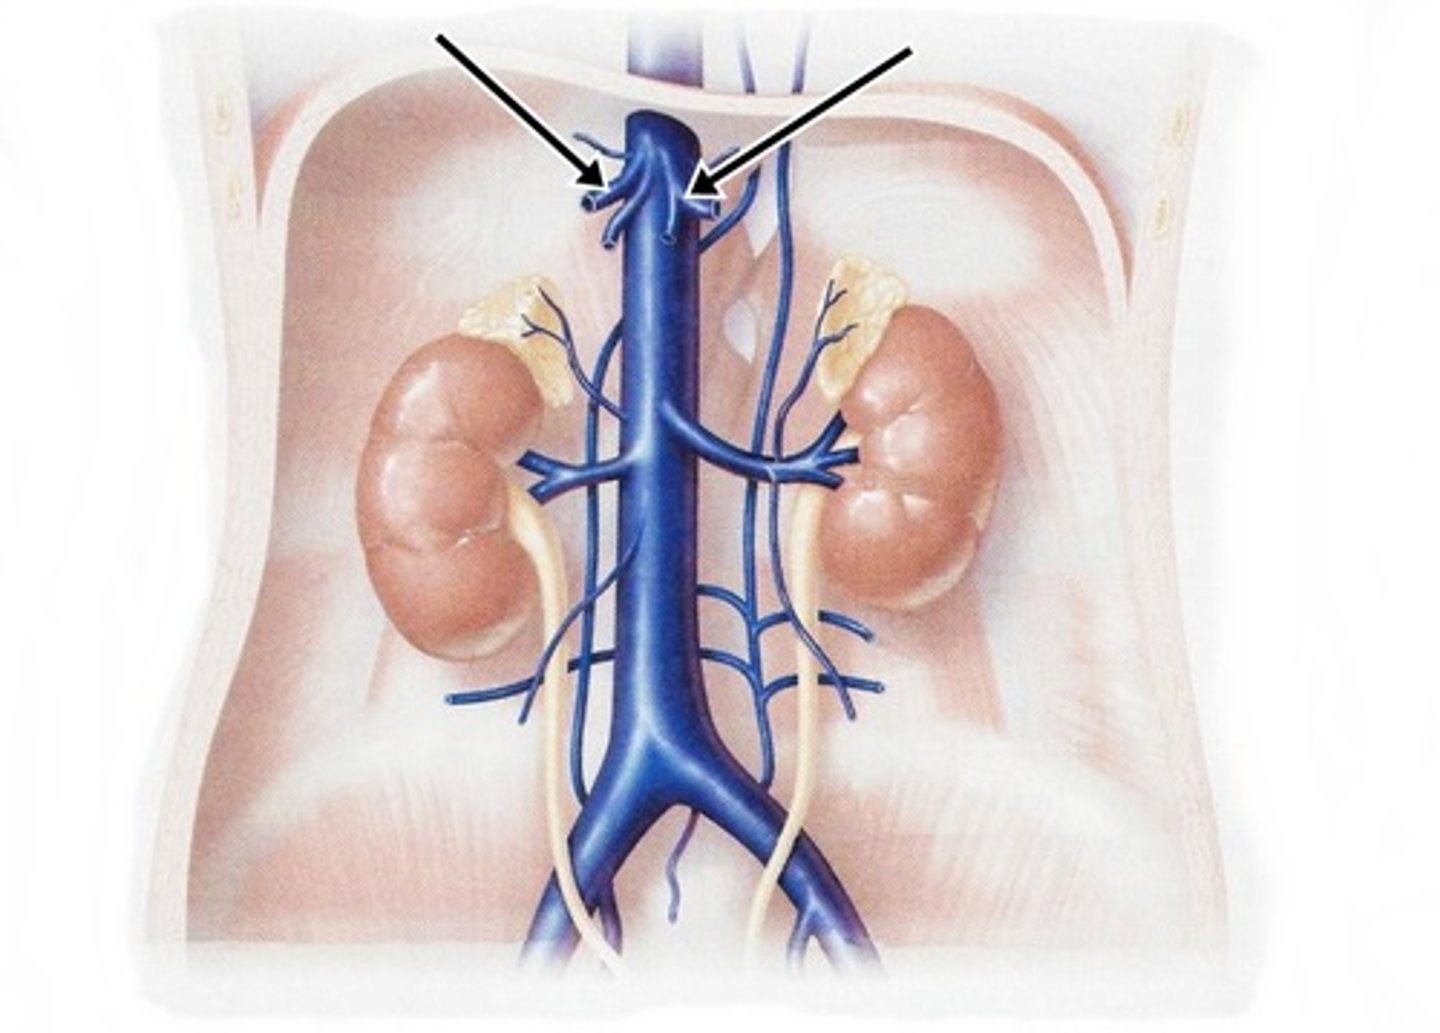

inferior vena cava

renal veins

left gonadal vein

right gonadal vein

renal artery

serves the kidneys

gonadal artery

serves reproductive organs